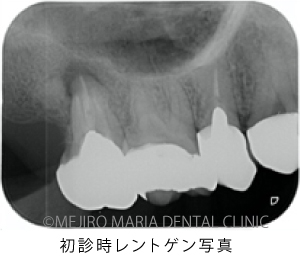

右上の奥歯付近に“できもの”ができたことを主訴に来院された患者様の症例です。当院での診査の結果、右上7番の根尖性歯周炎と診断しました。しかし、一部に限局的に進行している歯周ポケットが確認できたため、歯根破折もしくは歯内歯周病変が疑われました。患者様は診断的な意味合い(歯根破折の確認)も含め、被せものを外して精密根管治療を開始することを希望されました。

精密根管治療の開始後、根管内充填物(感染物)を除去して根管内を確認すると、歯根破折が見られました(中央写真の赤矢印)。歯根破折は根管内に留まっていましたが、歯周ポケットと繋がっていたため、1回目の治療を中止しました。